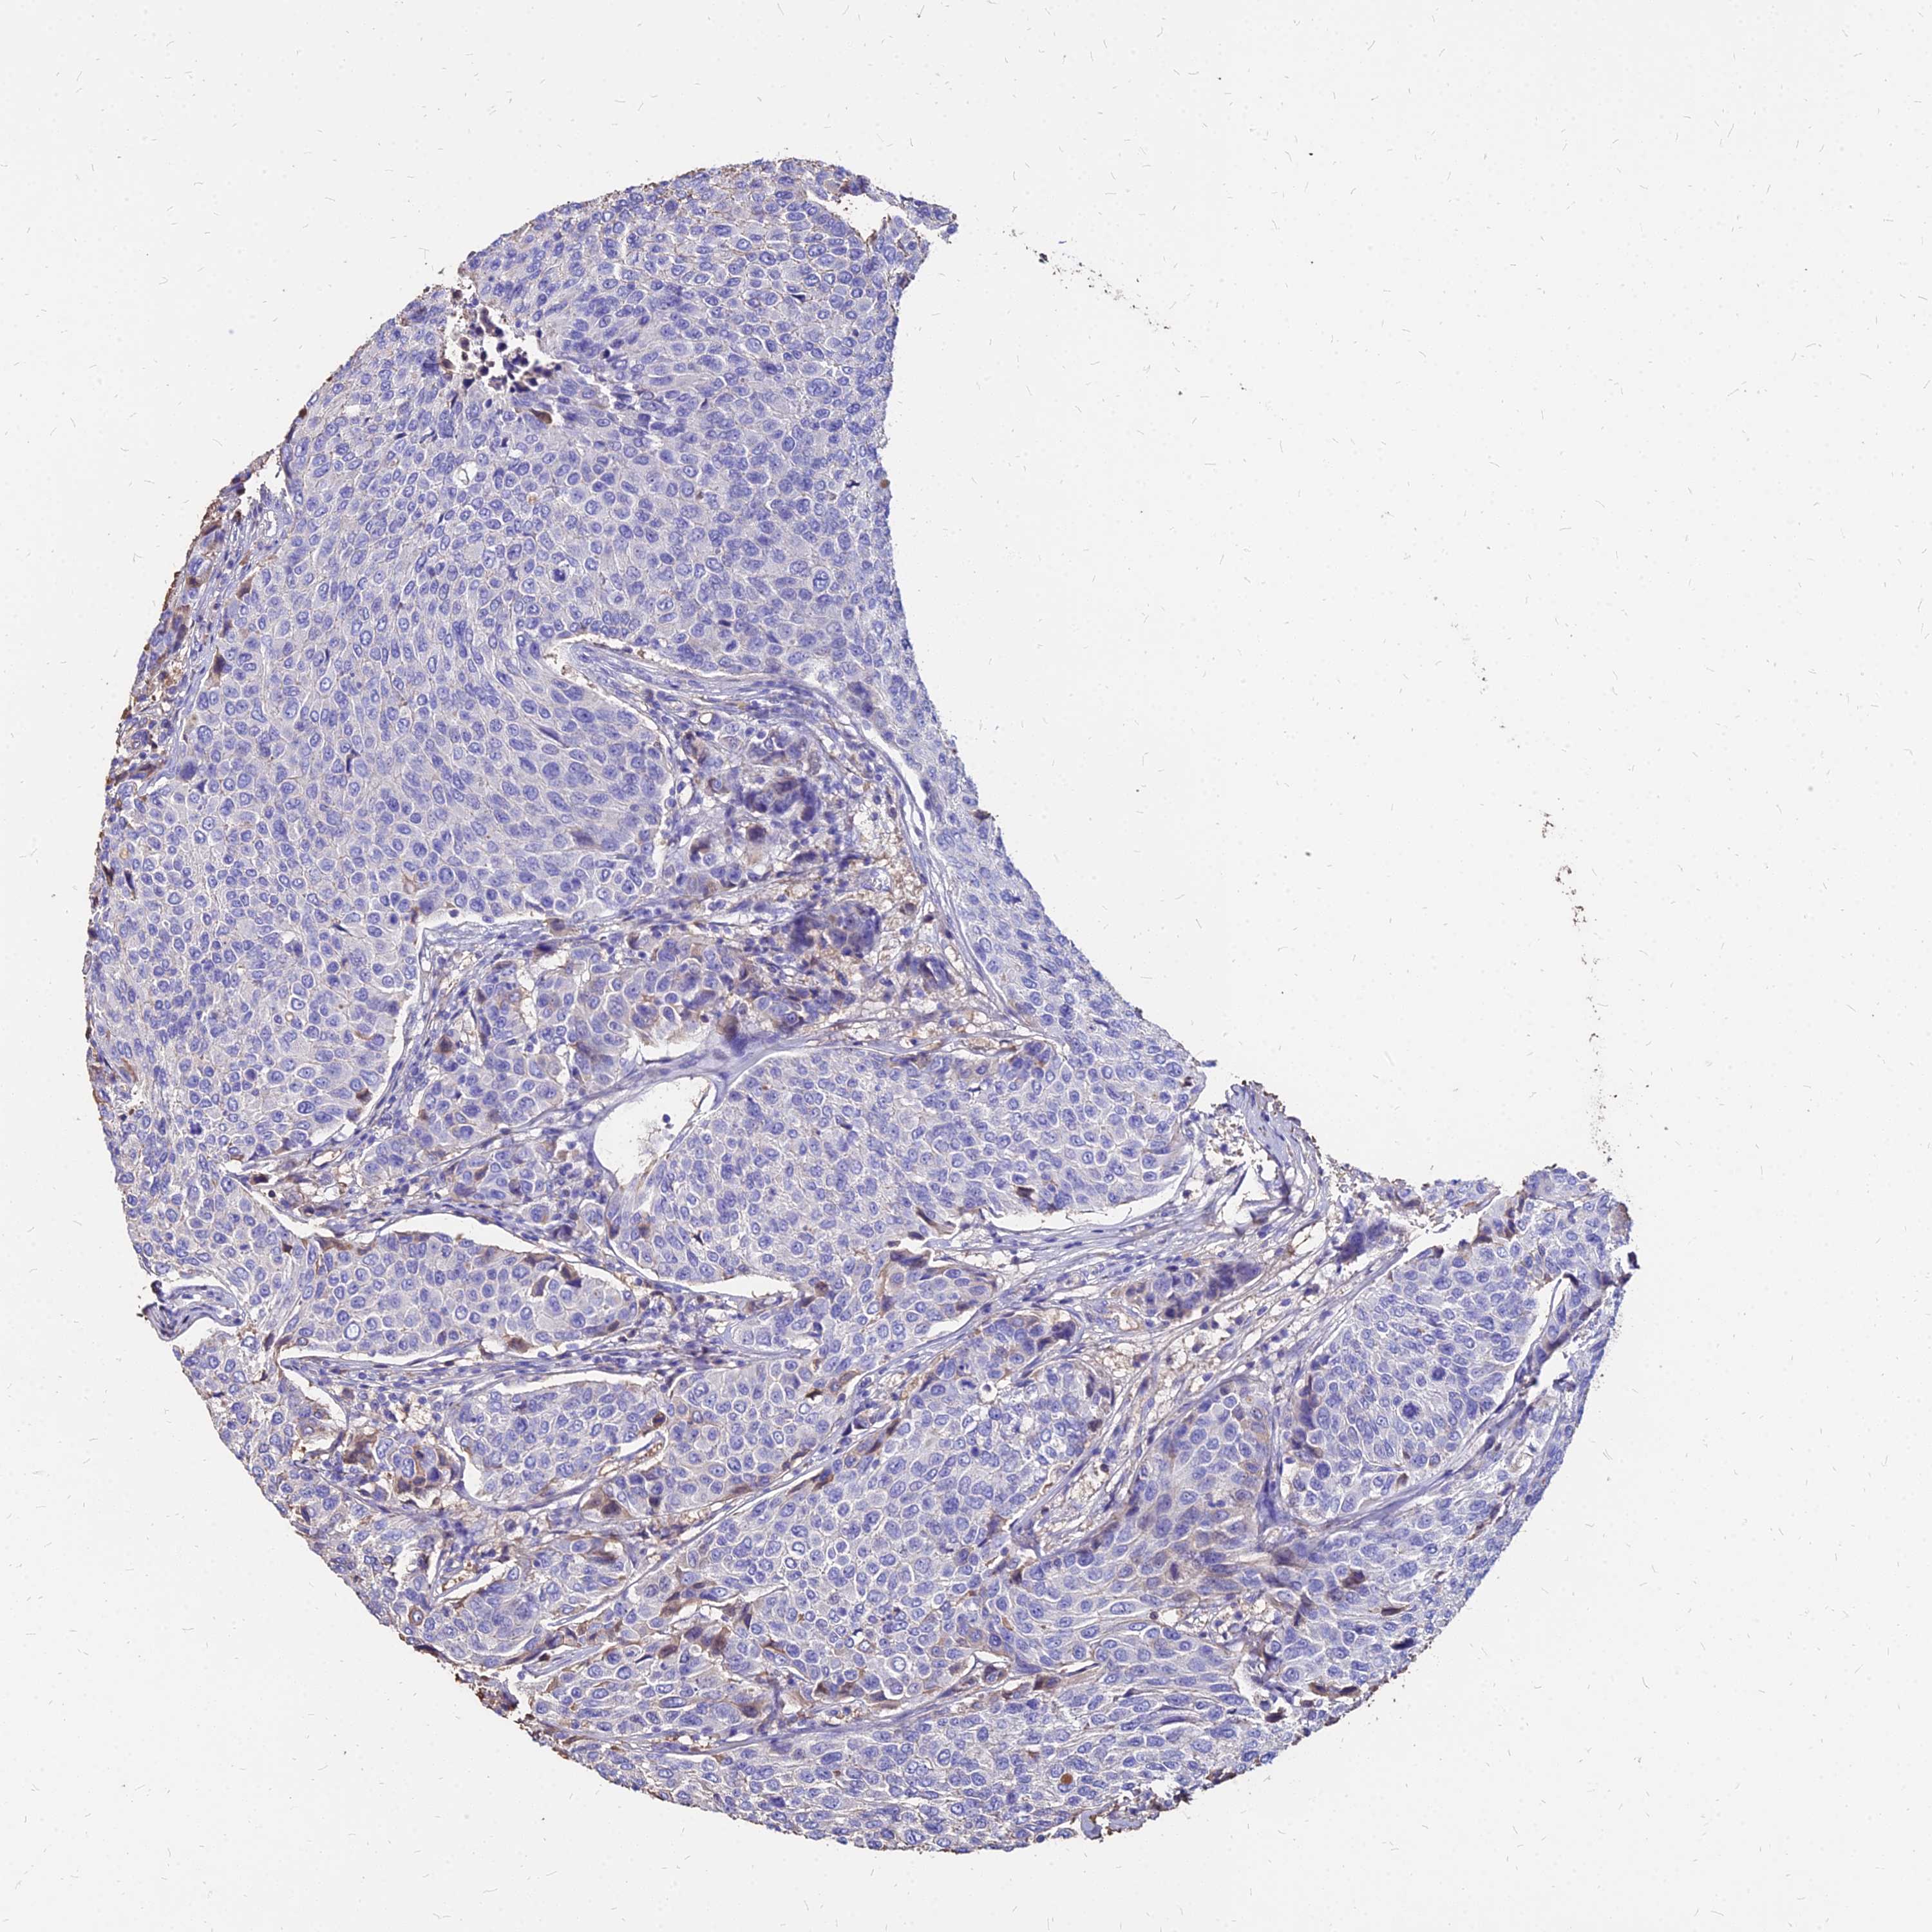

BRCA TCGA BRCA VALIDATION PROTEIN EXPRESSION

Breast cancer

Human cancer